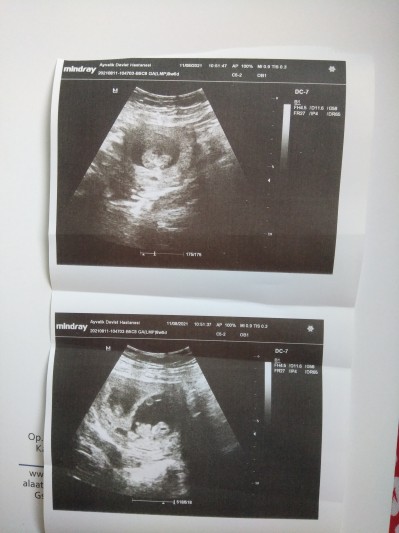

Merhaba Anneler Bugün devlet hastanesinde ikiz bebeklerimi kontrole gittim 2 hafta önce kalp atışlarini ikisininde duymuştum . Bugün önce Üstteki bebeğin kalp atışlarını açtı doktor daha sonra alltaki bebekte kalp atışı yok dedi.  Kalp atışı alamıyorum duyamıyorum biraz kurcaladiktan sonra kalp atışı var ama pozisyonundan dolayı duyamıyorum bak kalbi burda falan dedi ama bişey göremedim acaba başından mı savdı beni normal mi böyle bişey . Bi de İki bebeği aynı kareye siğdirmayi beceremedi aynı anda göremiyorum dedi fotoğraf istedim tek tek çekti. Hangisi üstte hangisi alltaki belli mi lütfen yardımcı olun kalp atışı var dedi ama dinletmedi . Üst resimdeki bebek sanki daha küçük gibi gelişimi geri mi kalmış kalbi durdugu için mi oldu acaba çok üzgünüm :(

Gebelik haftası 9